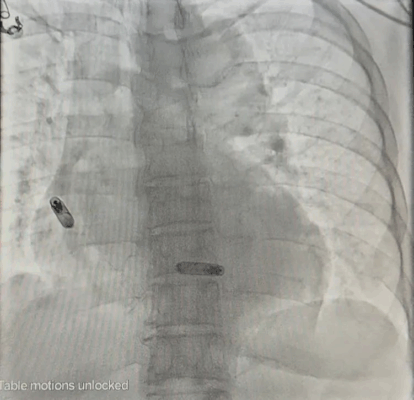

AVEIR™ DR手术成功影像图